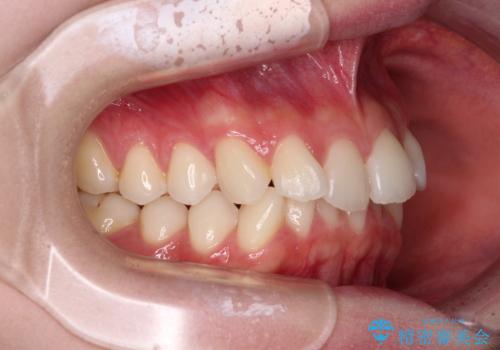

前歯のデコボコと深い咬み合わせ インビザラインできれいに改善

インビザラインによる上下歯列の拡大と、IPR(歯と歯の間を削る)にるスペースの獲得により、口元のデコボコとディープバイトを改善することとしました。

インビザラインは、装着していない時間がどれだけ短いかが、治療期間を大きく左右します。こちらの患者様は1日22時間以上、毎日欠かさず装着してくださったため、1年弱という短期間で満足のいく歯列に整えることができました。